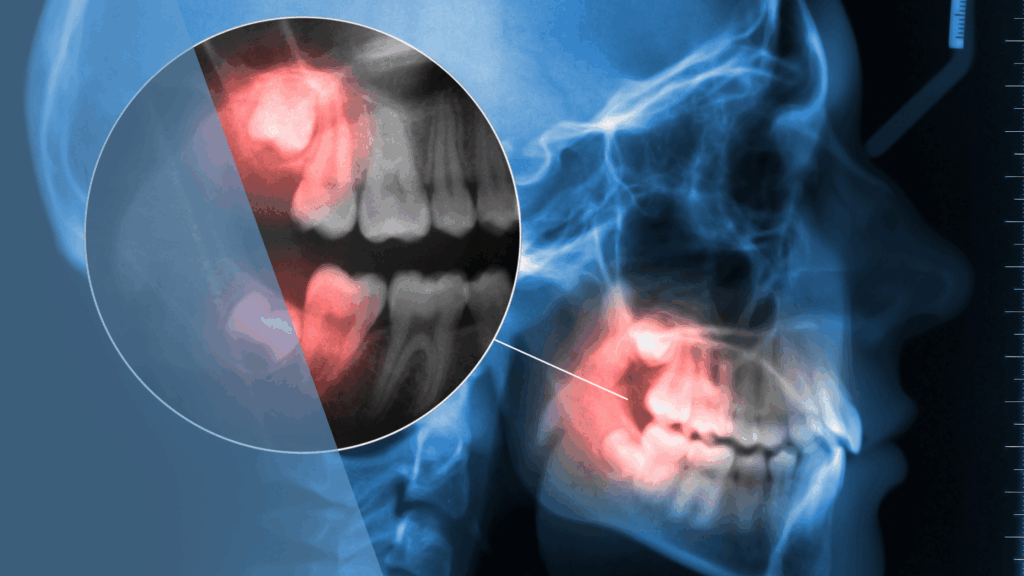

The Complete Guide to Wisdom Teeth Extractions: Before, During, and After

Planning wisdom teeth extractions? This comprehensive guide from Dental Arts Toronto covers pre-operative preparation, the step-by-step procedure, anesthesia options, and detailed recovery timeline to help you know exactly what to expect.